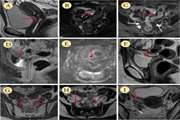

LongTerm Clinical and Imaging Findings in Patients with Lower Extremity Varicose Veins Treated with Endovenous Laser Treatment: A Follow Up Study of up to 12 Years 1403/12/26 - 08:23